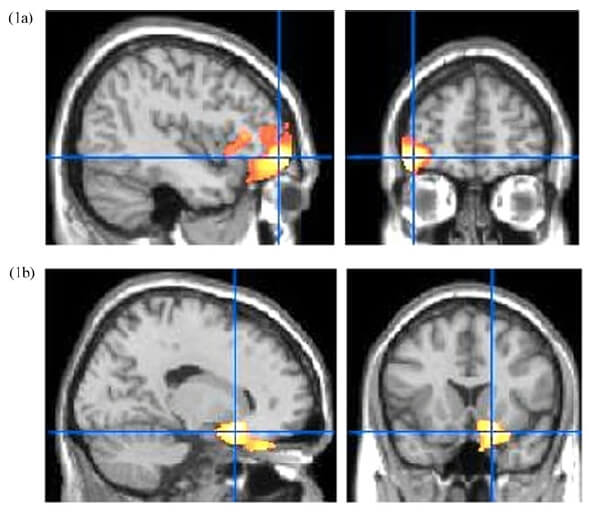

研究結果發現,吼叫雖然沒有實質上的身體接觸,長期下來也會嚴重傷害兒童腦部發展。這些受到父母嚴厲教養的兒童,大腦的「前額葉皮層」和「杏仁核」較小,這兩個區塊主要是是人體調節情緒和焦慮的關鍵中樞。若該部位萎縮,會增加罹患憂鬱、躁鬱的機率。

長期受嚴苛教育的孩子前額葉皮層和杏仁核較小。圖片來源 /《Development and Psychopathology》